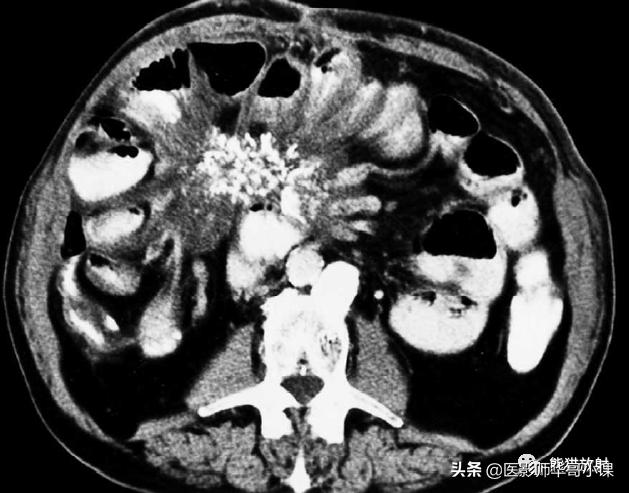

包虫病主要是感染细粒棘球绦虫所致。腹膜包虫病常常由于肝包虫病外伤或手术破裂而发生。 腹膜出现囊状占位性病变,囊壁薄,常有分隔 。腹膜种植时CT是首选检查方法(图)。边缘环形钙化具有提示诊断意义。

腹膜包虫病。增强CT显示一个大而多分隔的囊性腹膜肿块。囊内见子囊,多发分隔的蜂窝状表现,边缘钙化为其特征性表现。